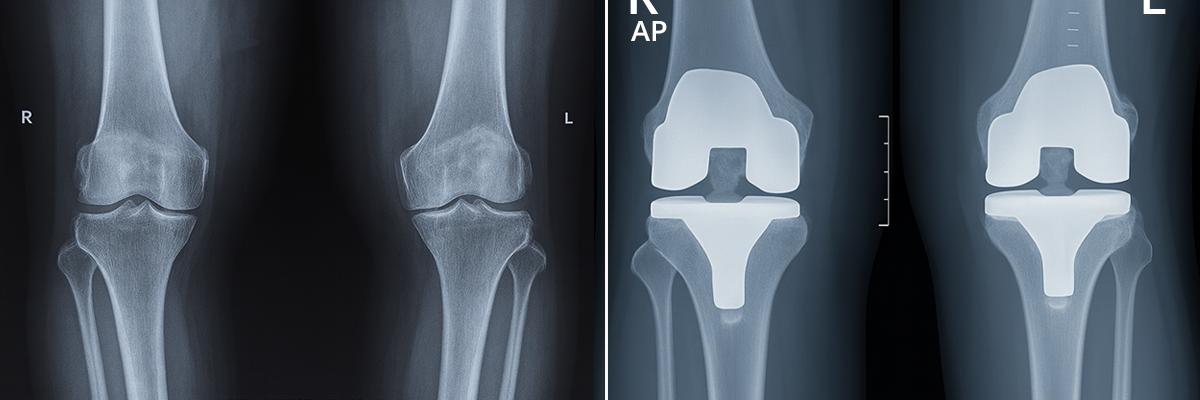

1. Joint Resurfacing with Advanced Materials

Primary Knee Replacement involves resurfacing the damaged cartilage in the knee joint. The worn-out surface is replaced with high-quality metal, ceramic, or polyethylene implants for smooth movement and pain relief.

5. Durable Implant Materials Used

The implants used are made of Cobalt Chrome, Titanium, Oxinium, and Medical-Grade Polyethylene, all designed for biocompatibility and long-lasting performance.